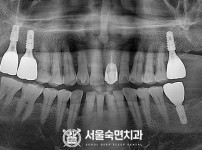

임플란트-전후사진4